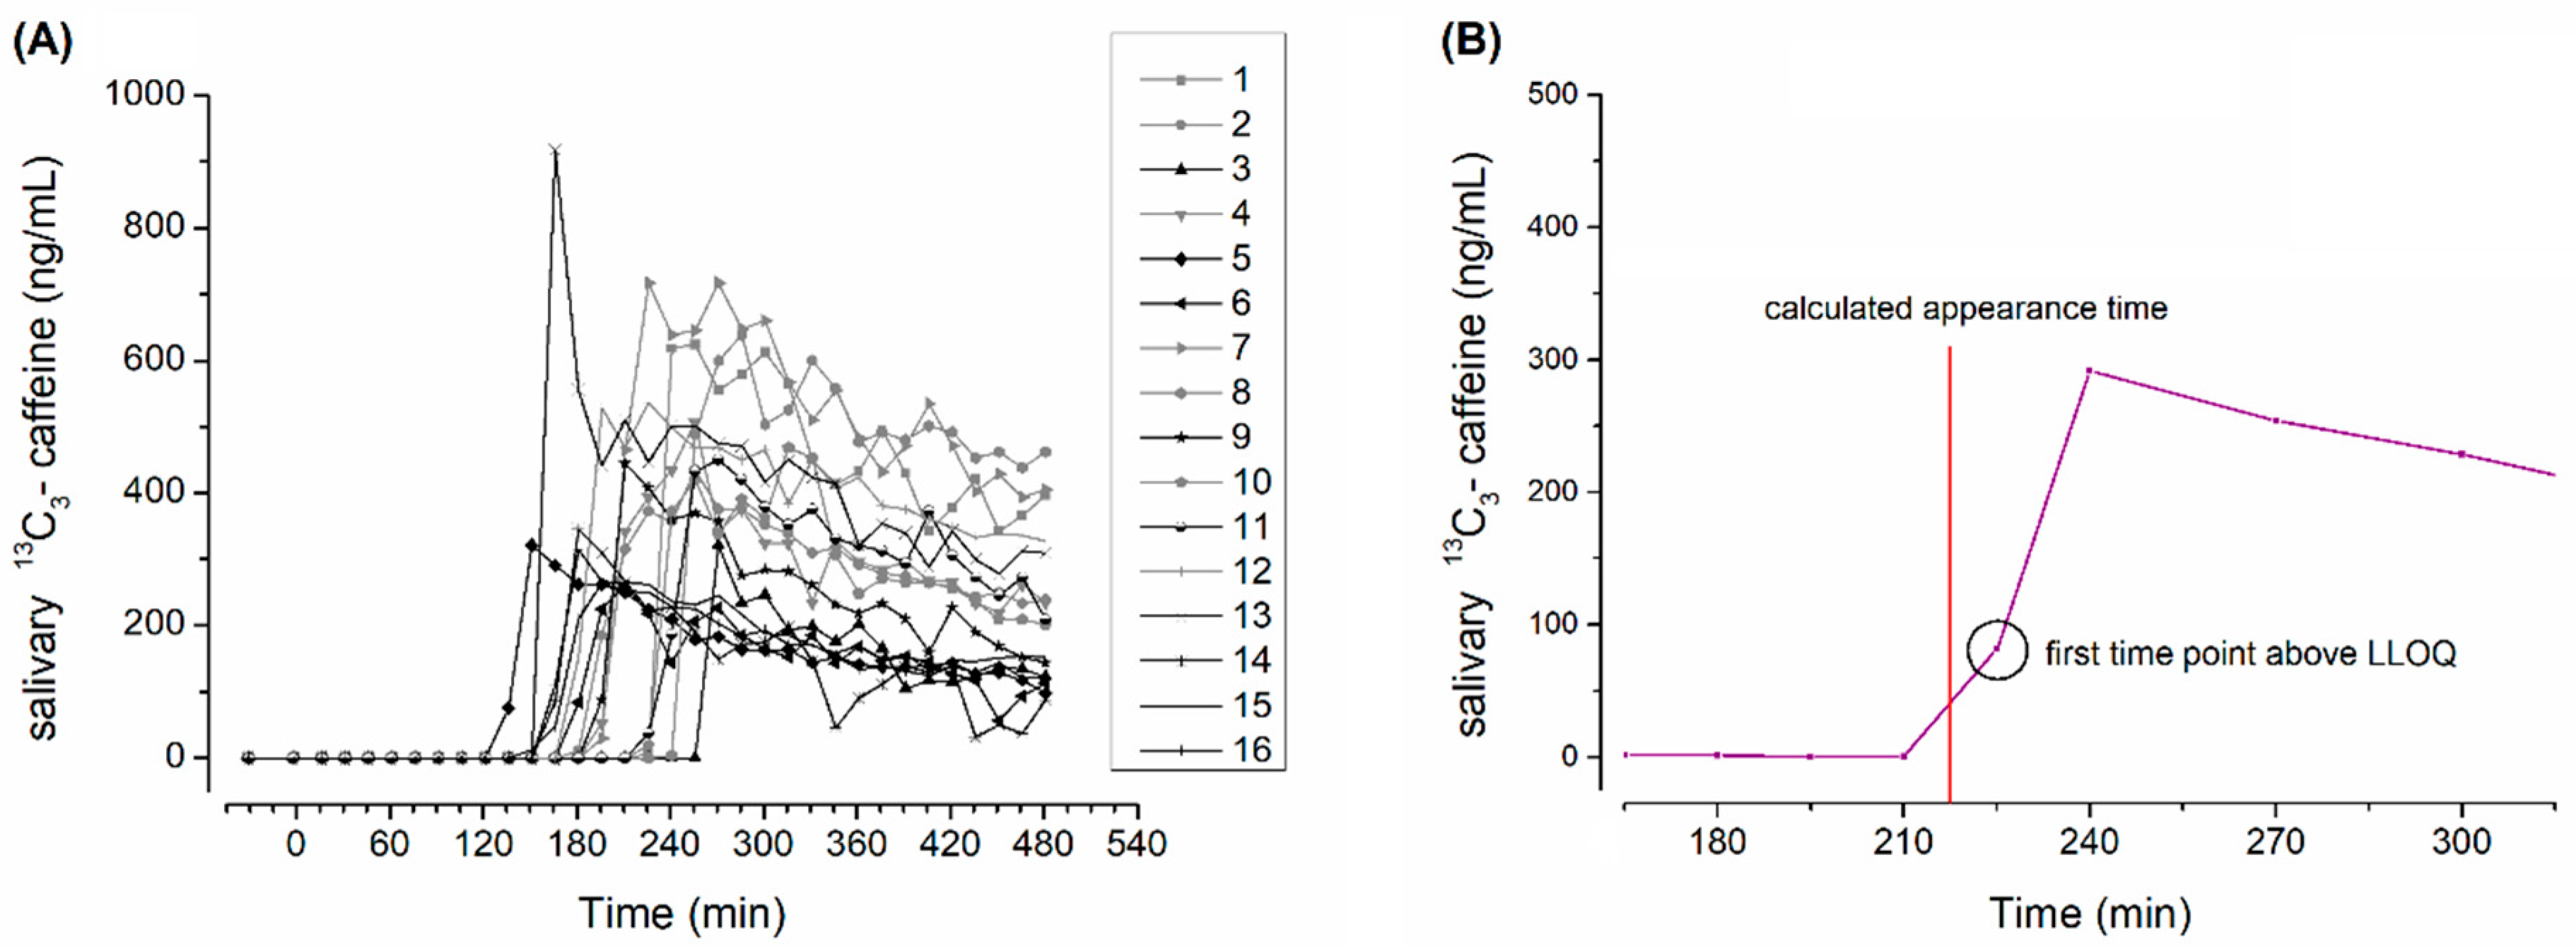

2.4. Salivary Sample Preparation and Evaluation of Caffeine Pharmacokinetics

2.5. Magnetic Resonance Imaging Sequences

3. Results and Discussion